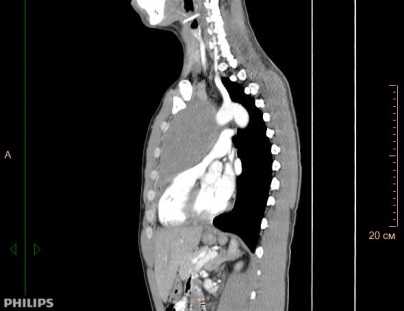

Рисунок 1б. Компьютерная томография пациента К, 31 лет с медиастинальным образованием (НМИЦ онкологии им. Н.Н. Петрова), сагитальная плоскость.

При поражении органов средостения рентгенологическая и клиническая картина неспецифичны (рис.1), только развернутый гистологический диагноз позволяет определиться с тактикой и подобрать эффективную терапию.

КТ ОГК. Объемное образование в средостении (патологически измененный лимфоузел), подтвержденная лимфома.